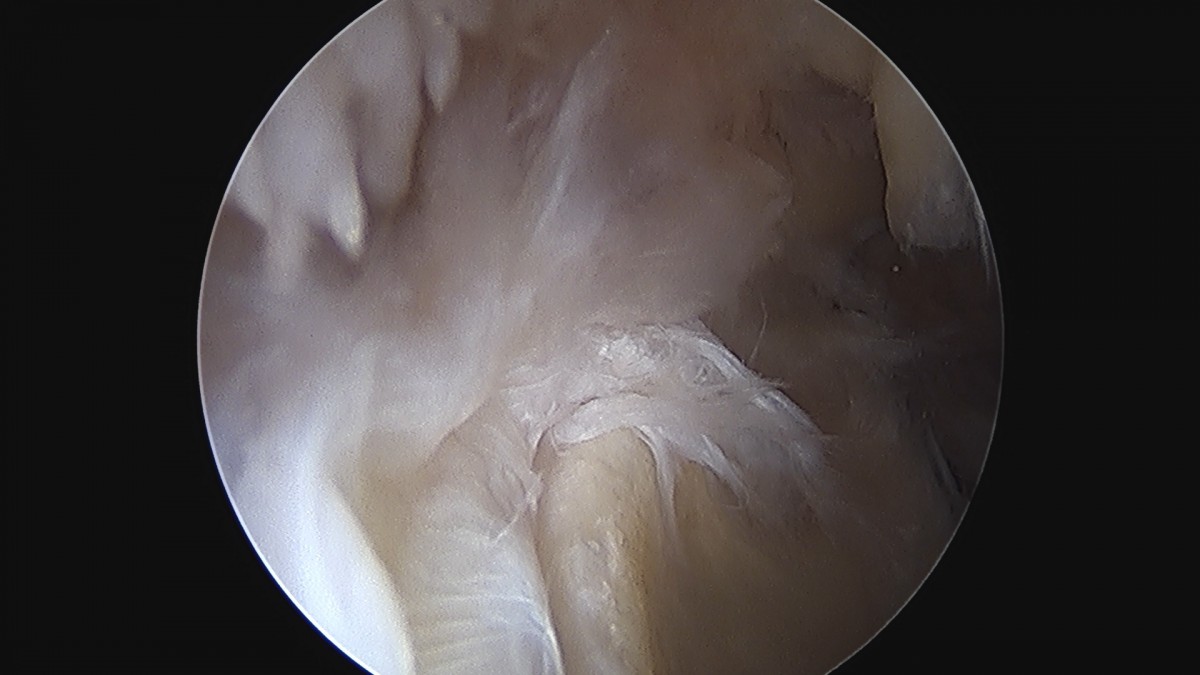

정지영원장님 어깨 회전근개 봉합술 임채O 환자

dae765e4d9ac96aee867c9d6292d8784_1758009113_1082.jpg